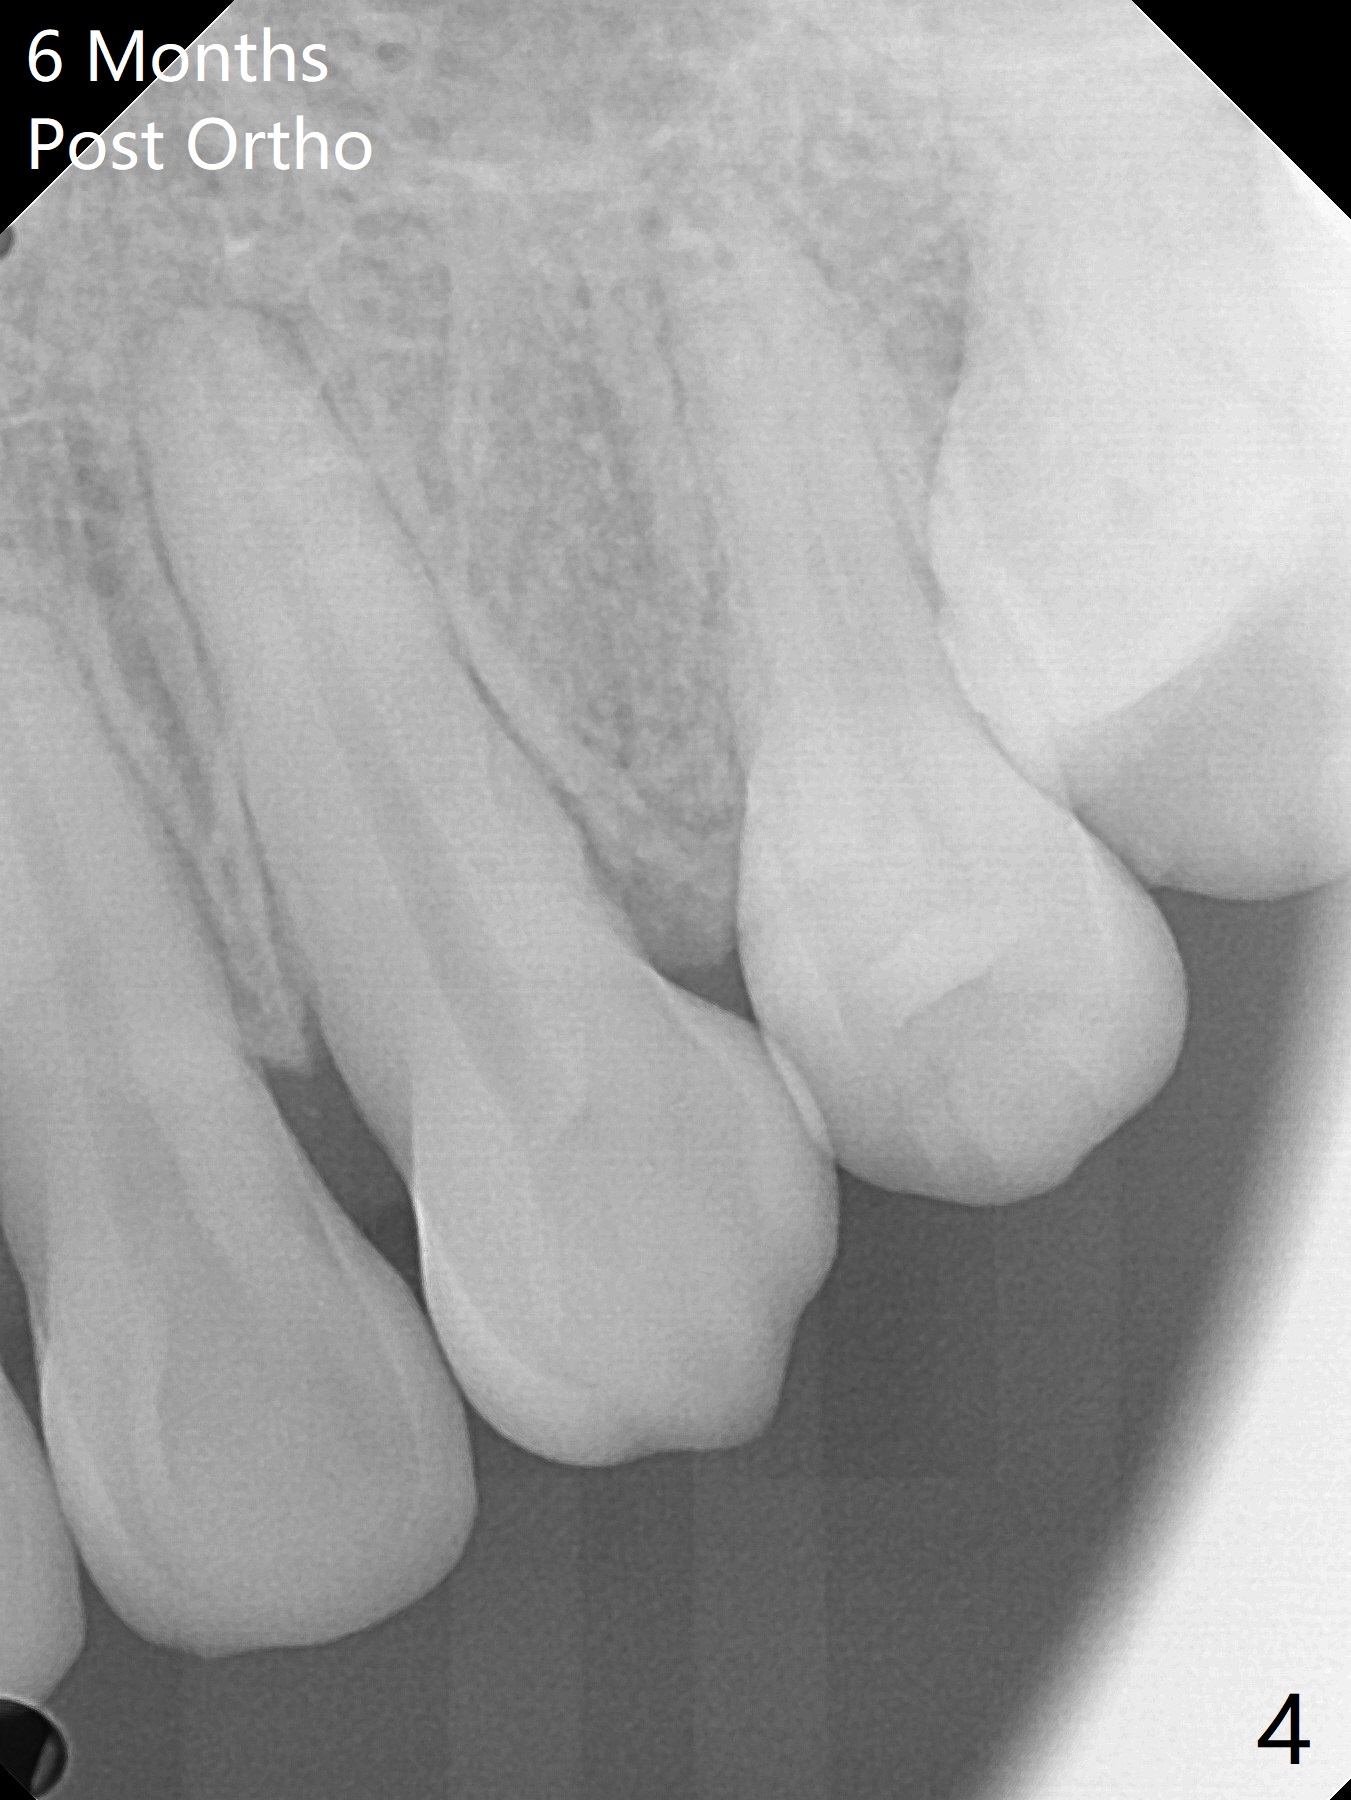

A 41-year-old woman with crowding (Fig.1) undergoes 2.5 year orthodontic treatment with extraction, leading to root resorption of the maxillary anterior teeth (Fig.2-4).